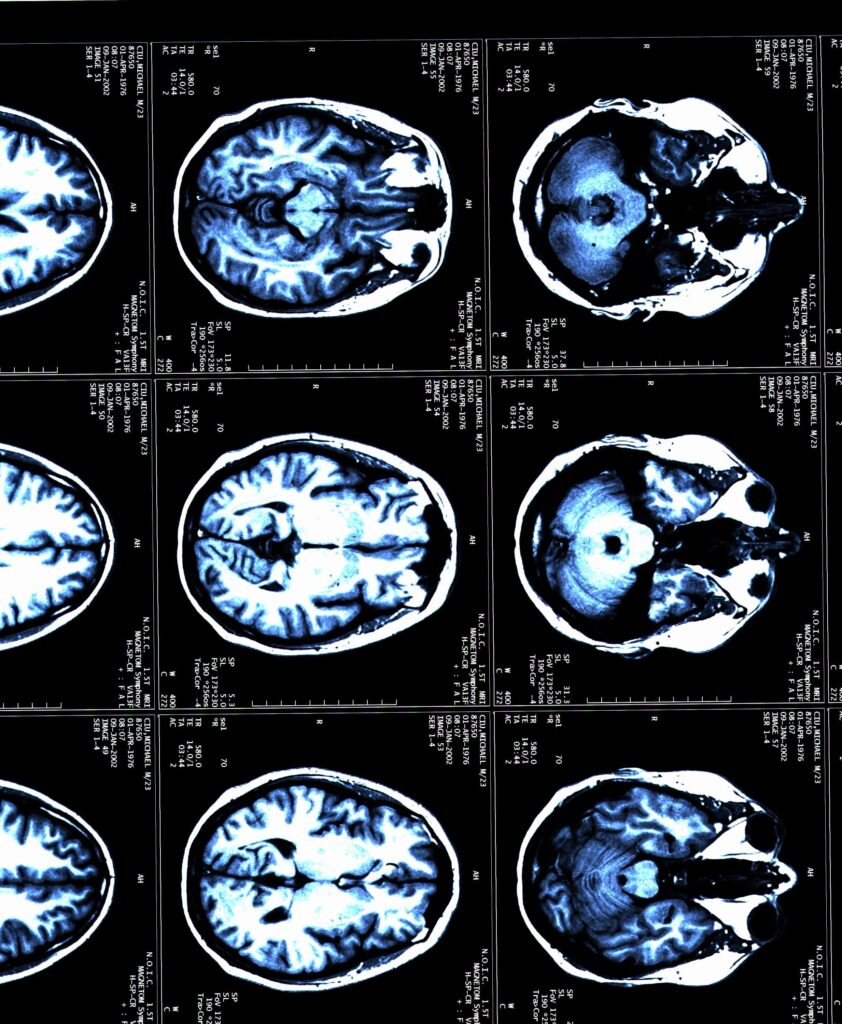

3. Magnetic Resonance Imaging (MRI)

MRI scans are pivotal in the MS diagnostic process. They provide detailed images of the brain and spinal cord, revealing lesions or areas of demyelination that suggest MS. Neurologists often use MRI scans to look for evidence of damage in multiple areas of the central nervous system that occurred at different times. The use of contrast material (gadolinium) can help distinguish between old and new lesions, offering insights into the disease’s activity.